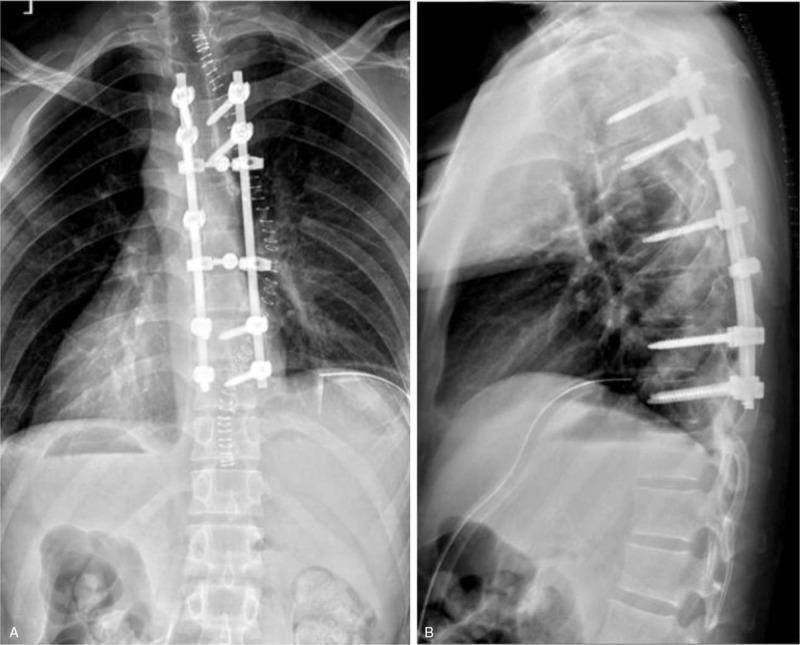

The patient underwent thoracic spinal canal decompression, complete tumor resection, pleural defect repair, and T4 to T10 internal fixation procedure via a posterior approach.

The patient's symptom improved significantly after the surgery, and the postoperative period was uneventful at the 2-year follow-up visit. There were no complications associated with the operation during the follow-up period.

患者通过后路接受了胸段椎管减压、肿瘤完整切除、胸膜缺损修复以及T4至T10内固定手术。

术后患者症状明显改善,在2年的随访期内术后恢复顺利。随访期间无手术相关并发症。